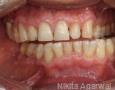

Pictures

Baseline